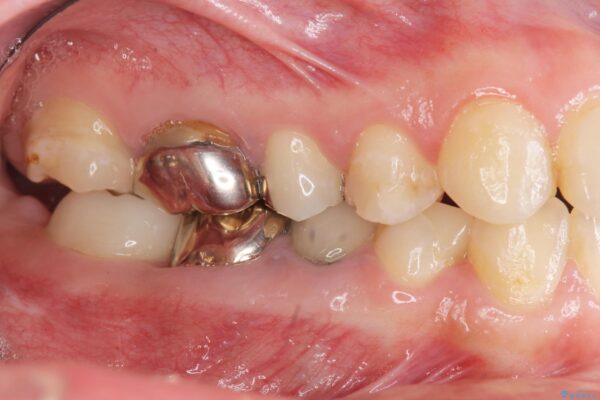

治療中

遊離歯肉移植術を伴うインプラント治療 治療中画像 遊離歯肉移植術を伴うインプラント治療 治療中画像 遊離歯肉移植術を伴うインプラント治療 治療中画像 遊離歯肉移植術を伴うインプラント治療 治療中画像 遊離歯肉移植術を伴うインプラント治療 治療中画像 遊離歯肉移植術を伴うインプラント治療 治療中画像